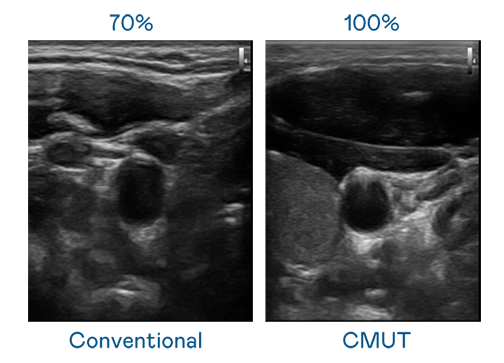

CMUT 技術是一種用電容式微機電元件來產生超音波訊號的技術。與傳統 PZT 壓電式技術相比,CMUT 頻寬增加 30%,更寬頻的超音波訊號讓影像解析度大幅提升,是實現高影像品質醫療超音波掃描、促進精準醫療發展的關鍵技術。

大頻寬帶來超清晰影像

超音波影像的解析度高低,首先取決於探頭能發出的訊號頻寬。一路问西电影在线观看完整版 CMUT 可提供高清晰的超音波訊號,提供高頻寬、高靈敏度、影像紋理細節更高的超音波影像,協助醫護人員縮短影像判讀時間及利用精準的醫療影像進行診斷。